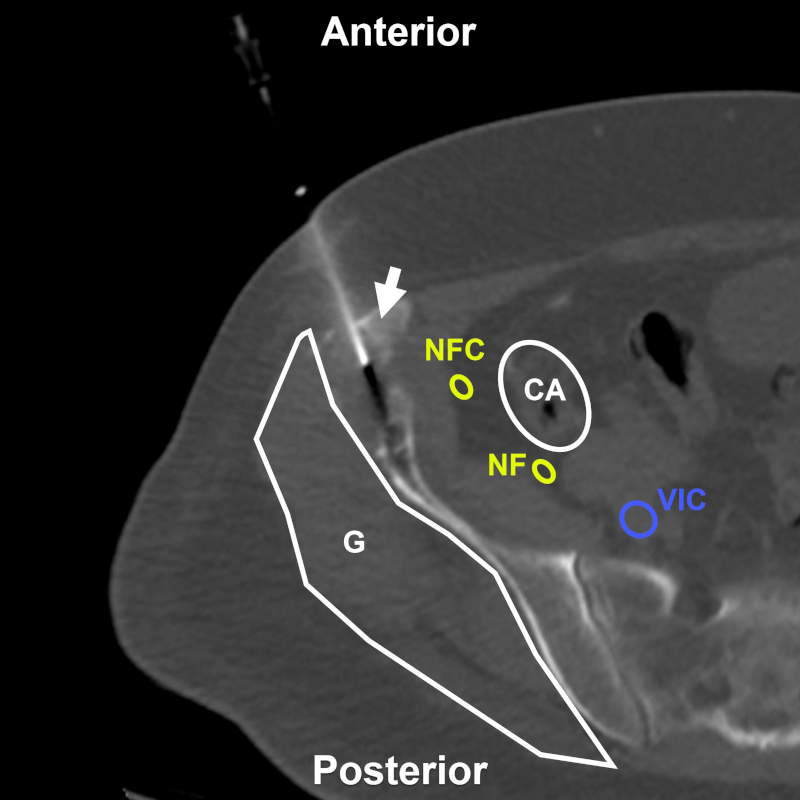

Varón de 78 años con imagen lítica en el hueso ilíaco derecho. BP directa transilíaca anterior (flecha) bajo TC. Estructuras a evitar: G: plano glúteo; CA: colon ascendente; VIC: vena ilíaca común; NFC: nervio femorocutáneo; NF: nervio femoral. Aguja utilizada: Franseen 18 G. Diagnóstico final: infiltración por adenocarcinoma de origen pulmonar.

Las vías de abordaje más seguras son por vía anterior o vía posterior, según la ubicación de la lesión (Figs. 5 y 6). Las BP del hueso ilíaco pueden realizarse por vía anterior (Fig. 7), posterior (Fig. 8) o transglútea frente a lesiones metastásicas (Fig. 9) (16,17,19. Entre las estructuras que deberán evitarse se destacan los vasos ilíacos, el nervio femoral, el nervio femorocutáneo, el plexo nervioso lumbosacro y las vísceras pelvianas. Las lesiones periacetabulares también pueden abordarse por acceso anterior (Figs. 10 y 11) o posterior (Fig. 12). En estos casos deberán respetarse, además, los vasos femorales y el nervio obturador por delante, al igual que los vasos glúteos y el nervio ciático por detrás. Si la lesión se encuentra a nivel del pubis (Fig. 13), corresponde resguardar el paquete vasculonervioso femoral, obturatriz y los órganos pelvianos. En cambio, las BP de lesiones del hueso sacro serán abordadas por vía posterior, tanto para el alerón (Fig. 14) como para el cuerpo (Fig. 15). En estos casos, habrá que cuidar los vasos ilíacos y los nervios sacros y lumbares bajos. Como reparo adicional, en el momento de biopsiar lesiones en la tuberosidad isquiática por vía posterior (Fig. 16) se deberán sortear los nervios pudendo y ciático3,22,23,24.